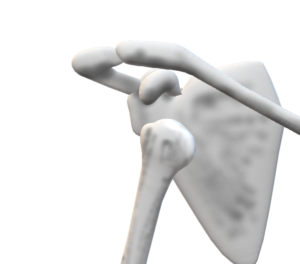

【柔整 各論】上腕骨外科頸外転型骨折

上腕骨外科頸外転型骨折 診察(必修)

発生

症状

・上腕軸の骨折端は内側に向き前内方凸変形